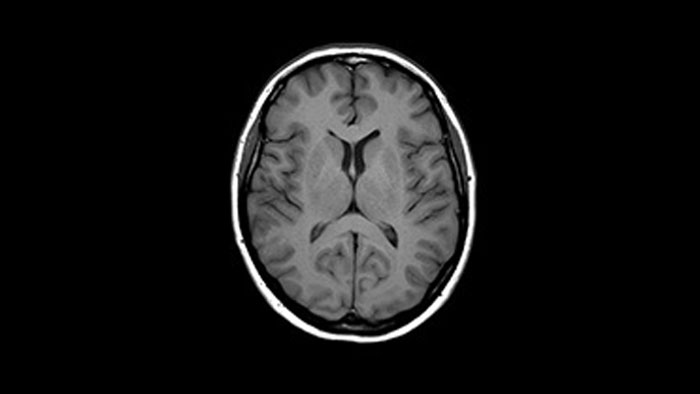

Bei einigen Untersuchungen, beispielsweise von Gehirn und Wirbelsäule, lässt eine hohe räumliche Auflösung sehr kleine Nerven und Gefäße besser erkennen. Um diese Auflösung zu erreichen, können mit Compressed SENSE 2D-MR-Scansequenzen durch schnellere 3D-Sequenzen ersetzt werden.

Mit Compressed SENSE lässt sich ein 2D-FLAIR-Scan mit einer Ausrichtung durch einen volumetrischen 3D-FLAIR-Scan mit mehreren Ausrichtungen ersetzen. Die Scandauer beträgt dabei lediglich dreieinhalb Minuten.

Ich erstelle häufig Bilder des Gehirns. Bisher haben wir die FLAIR-Sequenz mit einer Schichtdicke von 5 mm verwendet. Mit Compressed SENSE können wir jetzt einen volumetrischen 3D-Scan statt in sechs Minuten in etwa dreieinhalb Minuten durchführen.“

Dr. Mark Oswood, MD, PhD, Neuroradiologe, Hennepin Healthcare, Minneapolis, USA

Bei herkömmlichen MR-Scanmethoden bedeutet die Bildgebung mit hoher Auflösung mitunter eine lange Scandauer. Dies kann für Patienten mit Schmerzen oder Engegefühlen sehr schwierig sein. Auch für eine stark ausgelastete Abteilung ist eine lange Scandauer für hochauflösende Bilder möglicherweise nicht in den Zeitplan integrierbar. Compressed SENSE ermöglicht schnelle isotrope 3D-Bilder im Submillimeterbereich (0,7 mm oder weniger) in weniger als 5 Minuten, sodass auch herausfordernde Patientenfragestellungen und anatomische Strukturen zuverlässiger diagnostiziert werden können.

Dieser Fall demonstriert die Möglichkeit, zusätzliche Sequenzen zum selben Zeitfenster hinzuzufügen und so letztendlich die Diagnosesicherheit zu erhöhen. Neben klassischen TSE-Sequenzen ist im selben Zeitfenster auch eine funktionelle Sequenz mit diffusionsgewichteter Bildgebung möglich, die zusätzliche Informationen für die Diagnosestellung liefert.